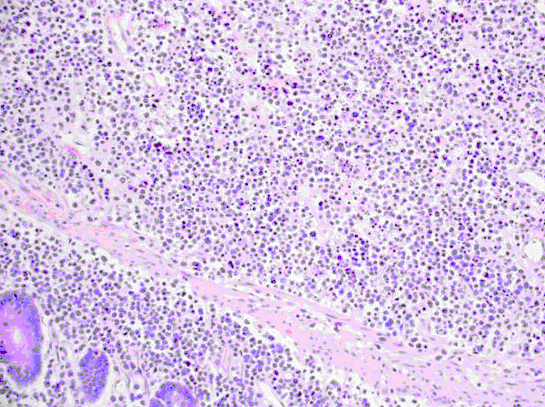

患者女,26岁,因“月经过多1年余”来诊。临床诊断:子宫黏膜下平滑肌瘤。宫腔镜检查见宫腔内赘生物3cm×2cm×2cm。行宫腔镜下“肌瘤”电切割术。肿瘤切面条纹欠清,质地中等,稍感细腻。

镜下图像如图所示,诊断首先考虑为()。